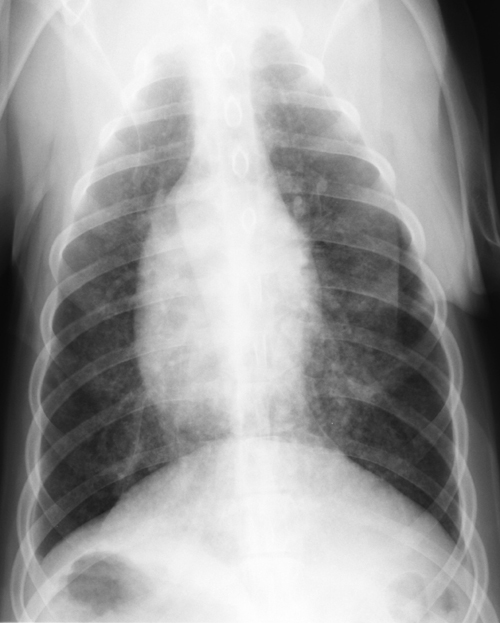

Klinik des SCLC